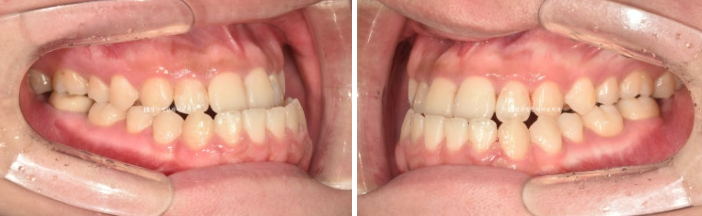

23.07~24.12

왼쪽은 초진이고, 오른쪽은 술전교정 마지막 모습입니다.

처음에 비하면 위 아래 앞니 간격이 오히려 더 커진 것 같은데요?

라고 말하실 수 있습니다.

술전교정에서는 주걱턱이 더 심해져 보이는 방향으로 치아를 움직여서 양악수술 직전 상태는 가장 부정교합이

심하고 불편한 상태가 됩니다.

그래야 수술 결과가 좋습니다.